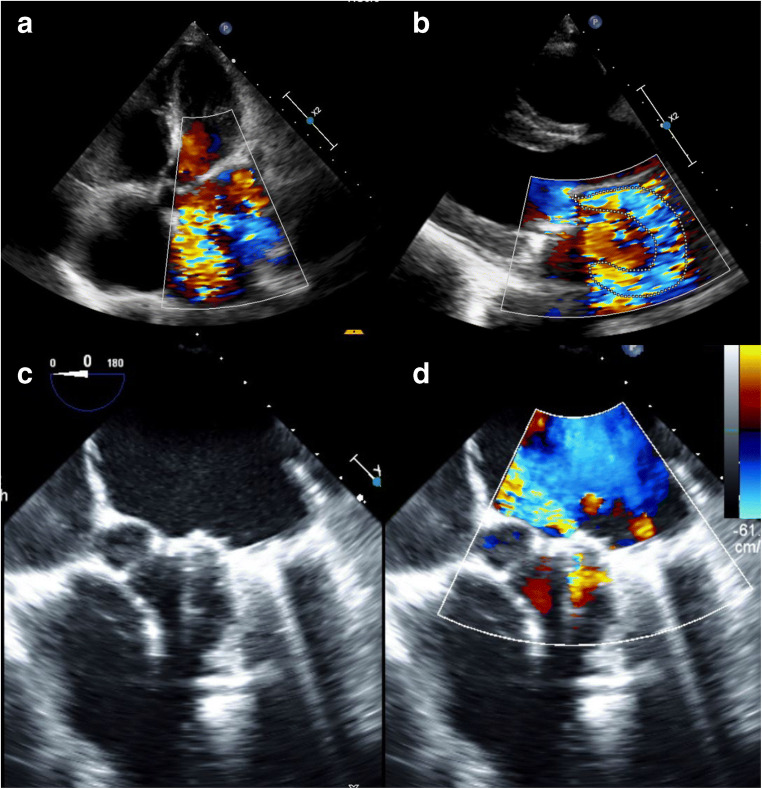

Fig. 2.

a, b Pre-operative echocardiogram showing severe prosthetic valve regurgitation. c Intraoperative transesophageal echocardiogram showing mitral valve prosthesis in systole with a component of the mitral prosthesis protruding into the left atrium. d Intraoperative transesophageal echocardiogram showing severe prosthetic valve regurgitation, possibly intra-valvular